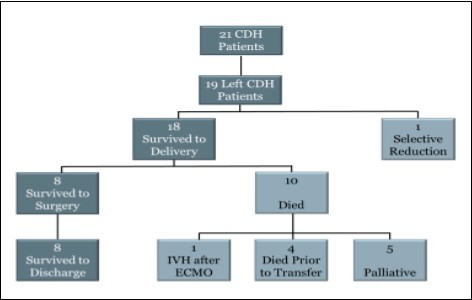

A total of 21 patients were identified with a prenatal diagnosis of CDH who had undergone both prenatal ultrasounds with LHR calculation, and a prenatal MRI with FLV calculation (Figure 3). Two of these patients were included in the accuracy of U/S LHR section, but excluded in the remaining analysis as they had either a right sided or bilateral CDH.

Figure 3.Flowchart showing outcomes of prenatally diagnosed CDH patients with both prenatal U/S LHR and MRI FLV obtained at Children’s Hospital of Wisconsin.

The remaining 19 patients that met inclusion criteria had a left-sided CDH. One patient was a diamniotic-dichorionic twin and underwent in utero selective reduction. Eighteen patients survived until birth. Eight patients survived to surgical repair, and all subsequently survived until discharge. Ten patients died after delivery. Four patients died before transfer to the Neonatal Intensive Care Unit. One patient was placed on extracorporeal membranous oxygenation (ECMO), which was complicated by a severe intracranial bleed. ECMO was stopped and the patient’s parents elected to withdraw care. Five patients were placed on palliative care after the family decided against or the patient was not found to be a candidate for ECMO. Of the five patients that were palliated, four had an initial pCO2 level greater than 80. One of these four patients, one had hypoplastic left heart syndrome, two had dextrocardia, the other patient had severe IUGR with a birth weight of 1800g at 34 weeks gestation (birth weight percentile of 8%). The remaining patient had an initial pCO2 of 66.1- however; the patient failed conventional ventilation, and was transitioned to HFOV with worsening acidosis. This patient had a birthweight of 2010 grams and was considered too small for ECMO, thus palliation was elected due to lack of further interventions.